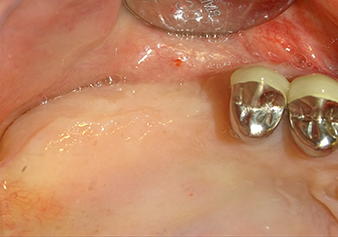

The I2A instrument (diameter 2.0 mm) was then used to perforate the sinus floor intermittently and on the smallest scale possible. This special piezosurgical method ensures that the Schneiderian membrane is not damaged. When the Z25P was used, the membrane was already lifted slightly by the coolant supplied via the instrument tip (Fig. 3). The coolant quantity was just 50% in order to avoid high pressure in the implant bed.

Implant bed preparation and augmentation

Following an intermediate check (Fig. 4) a further preparation step was performed (Fig. 5). Afterwards, the hydraulic Z35P instrument was used to lift the membrane to the desired position (Fig. 6 and 7). This was followed by further piezosurgical preparation of the implant bed, concluded with a rotary bur and shoulder milling cutter up to the implant diameter of 4.8 mm. Before the implant was inserted, the augmentation material (particle size approx. 0.8-1.6 mm) was introduced underneath the Schneiderian membrane (Fig. 8).